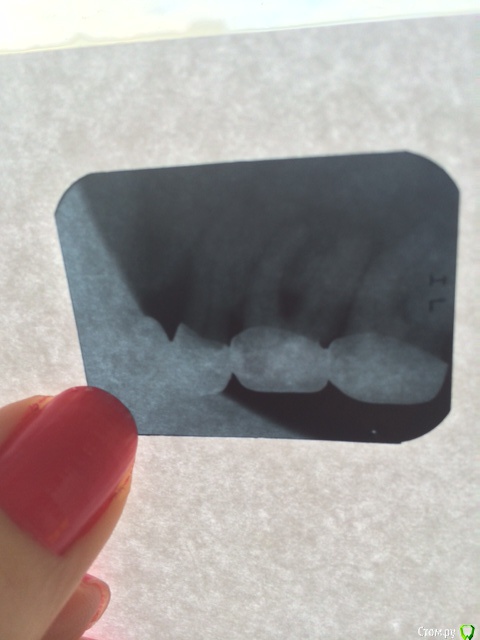

Rimmus Опубликовано 15 декабря, 2014 Поделиться Опубликовано 15 декабря, 2014 Добрый день.Прошу вашего компетентного мнения, есть ли вероятность сохранить зубы, которые рекомендуют удалять? Меня они не беспокоят, не болят, но слегка шатаются с недавнего времени. Зубы находятся под коронками. Хотела поменять коронки, но выяснила что под зубами вокруг корней разрушена костная ткань. Мнения врачей разделились, терапевты рекомендуют удалять, ортопеды не исключают возможности сохранить зубы, удалив из них нервы, но такие зубы прослужат недолго )) Или может быть их вообще не трогать? если они не беспокоят )) Но врачи говорят, что такие зубы провоцируют разрушение соседних здоровых зубов. Подскажите, пожалуйста, из трех зубов можно ли сохранить хотя бы два? И есть ли возможность восстановления костной ткани? Заранее спасибо! Ссылка на комментарий

red_butler Опубликовано 15 декабря, 2014 Поделиться Опубликовано 15 декабря, 2014 Снимок не читаем, перезалейте через радикал (вторая ссылка) и переснимите на фоне подсвеченного белого листа. А лучше сделайте цифровой панорамный снимок Ссылка на комментарий

Korel Опубликовано 15 декабря, 2014 Поделиться Опубликовано 15 декабря, 2014 Шестёрку удалять точно, снимок (вернее его качество) мешает что-нибудь сказать про два остальных. P.S. Маникюр симпатишный) 1 Ссылка на комментарий

red_butler Опубликовано 16 декабря, 2014 Поделиться Опубликовано 16 декабря, 2014 (изменено) http://s55.radikal.ru/i149/1412/41/a55e4c194f5a.jpgшестой зуб удалять Изменено 16 декабря, 2014 пользователем red_butler 1 Ссылка на комментарий

Cleric Опубликовано 21 декабря, 2014 Поделиться Опубликовано 21 декабря, 2014 Необходима тщательная диагностика. Я бы не спешил с удалением 6ки. Ссылка на комментарий